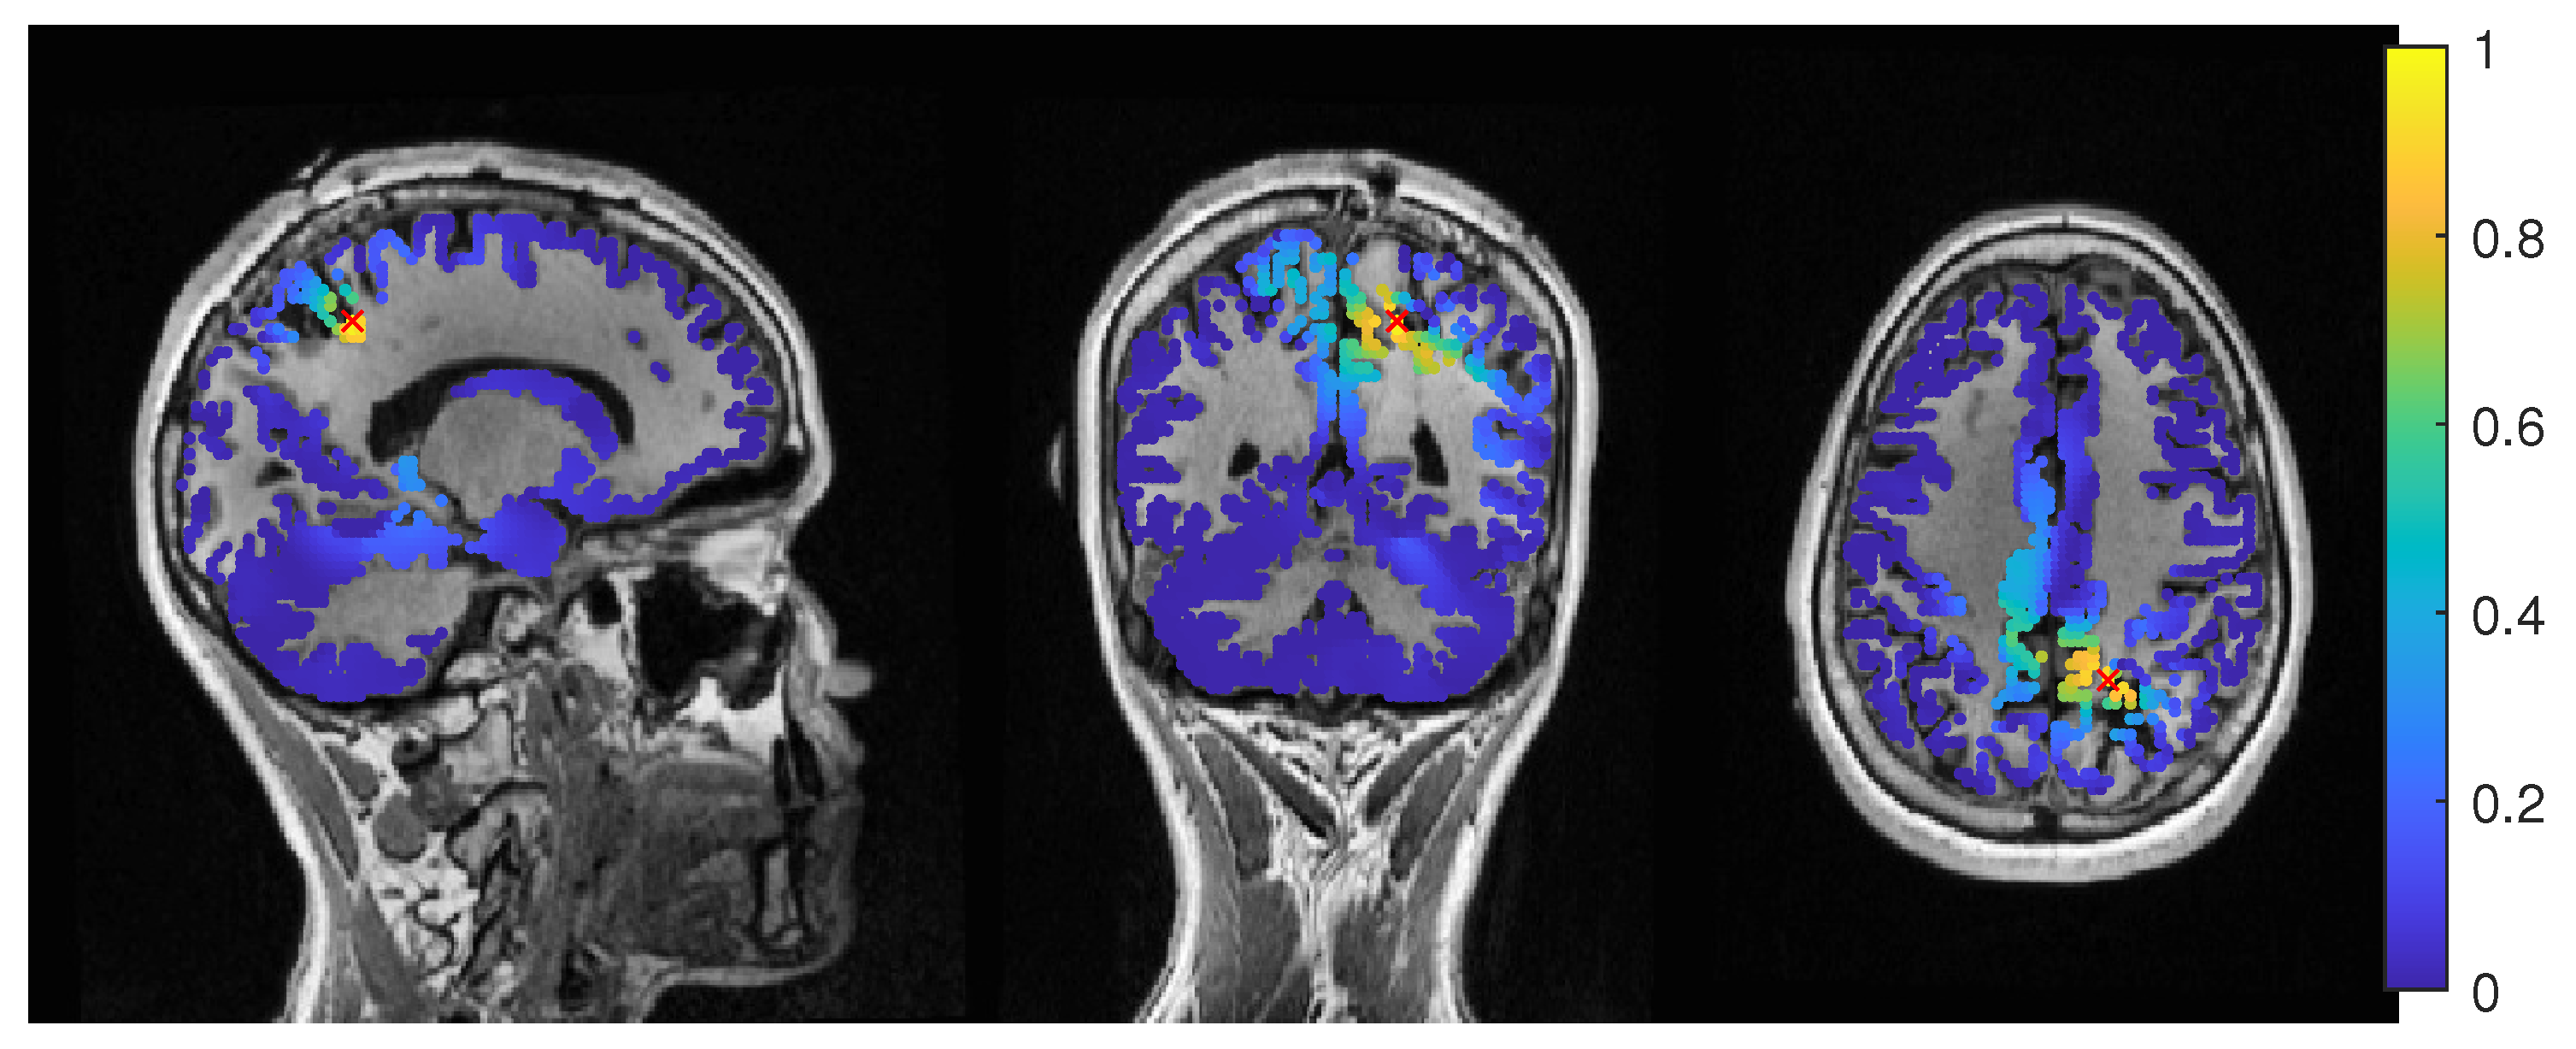

3.1.1. EEG

3.1.2. MEG

3.1.3. MEEG

3.2. Patient 2

3.2.1. EEG

3.2.2. MEG

3.2.3. MEEG